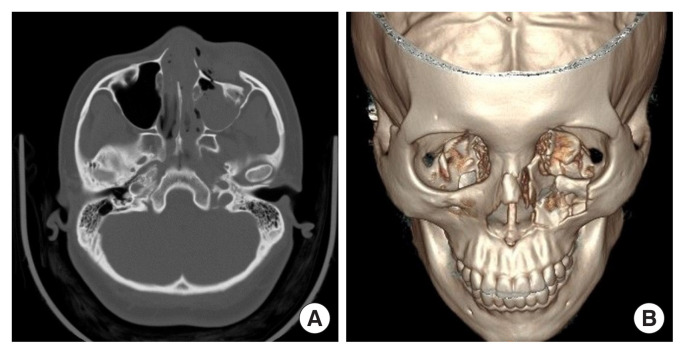

A 28-year-old woman presented to the emergency department with facial trauma. She had fallen from an electric scooter and complained of blurred vision in the left eye without diplopia. Left facial paresthesia was noted, and partial injury of the infraorbital nerve could be assumed considering a comminuted fracture around the infraorbital foramen. The patient had no previous history of trauma to the left periorbital area and had no underlying diseases. Computed tomography (CT) images demonstrated displacement of the left NOE complex (Fig. 1). In addition, a nasomaxillary buttress fracture was observed, nonetheless zygomaticomaxillary buttress was maintained. Ophthalmologists diagnosed preretinal and vitreous hemorrhage. The distance from the lateral orbital rim to the corneal apex in both eyes was the same as 17 mm. The distance from the facial midline to bilateral pupils was the same on both sides, and the interpupillary distance was 6.5 cm.

Fig. 1.

Preoperative computed tomography (CT) images. (A) Preoperative CT image demonstrating displacement of the left naso-orbito-ethmoid complex, axial view. (B) Preoperative three-dimensional CT image, bird’s eye view.